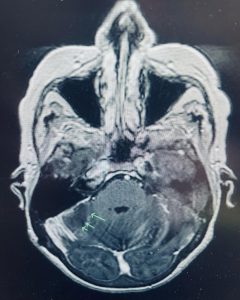

This female patient presented with dizziness and difficulty walking with a past history of colon cancer. Her brain MRI showed a metastatic tumor deep in her cerebellum. The pressure on the cerebellum was causing her balance issues. She had a craniotomy to remove the tumor. Microsurgery and stereotactic navigation were useful in this case given the tumor’s location deep in the brain. The tumor was completely removed (second picture, arrows), and her neurologic difficulties all resolved.